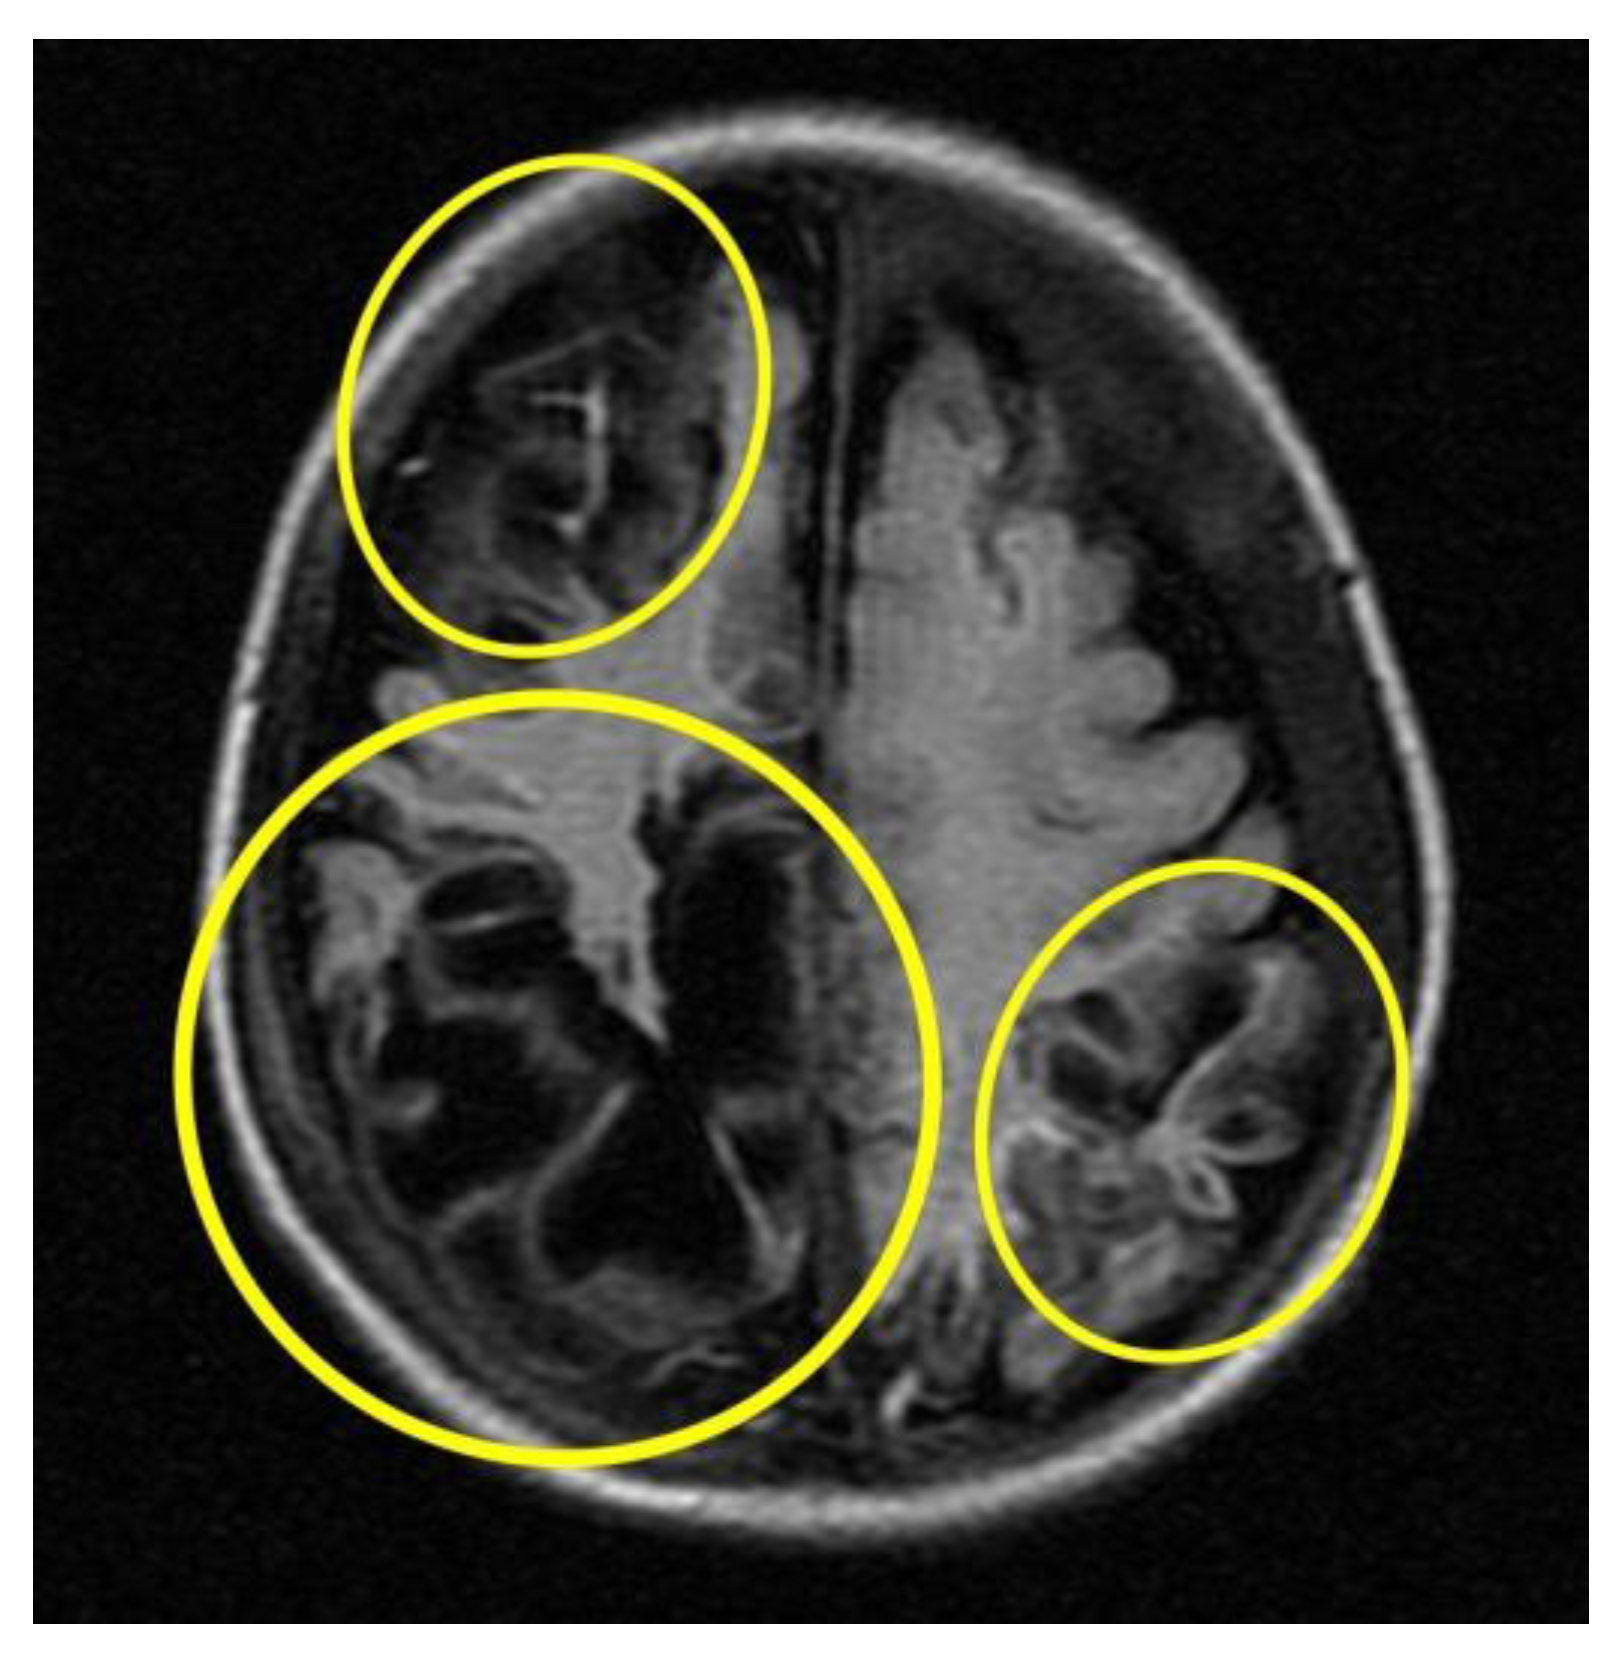

Subsequent instrumental investigations were performed on the baby to assess cranio-encephalic outcomes. In particular, the MRI (Figure 5) performed about a month after the presumed trauma revealed a picture characterised by cortical atrophy and cystic evolution of the brain parenchyma, mainly in the occipital region bilaterally.

Figure 5. MRI cortical atrophy and cystic evolution of the brain parenchyma (circles in yellow).